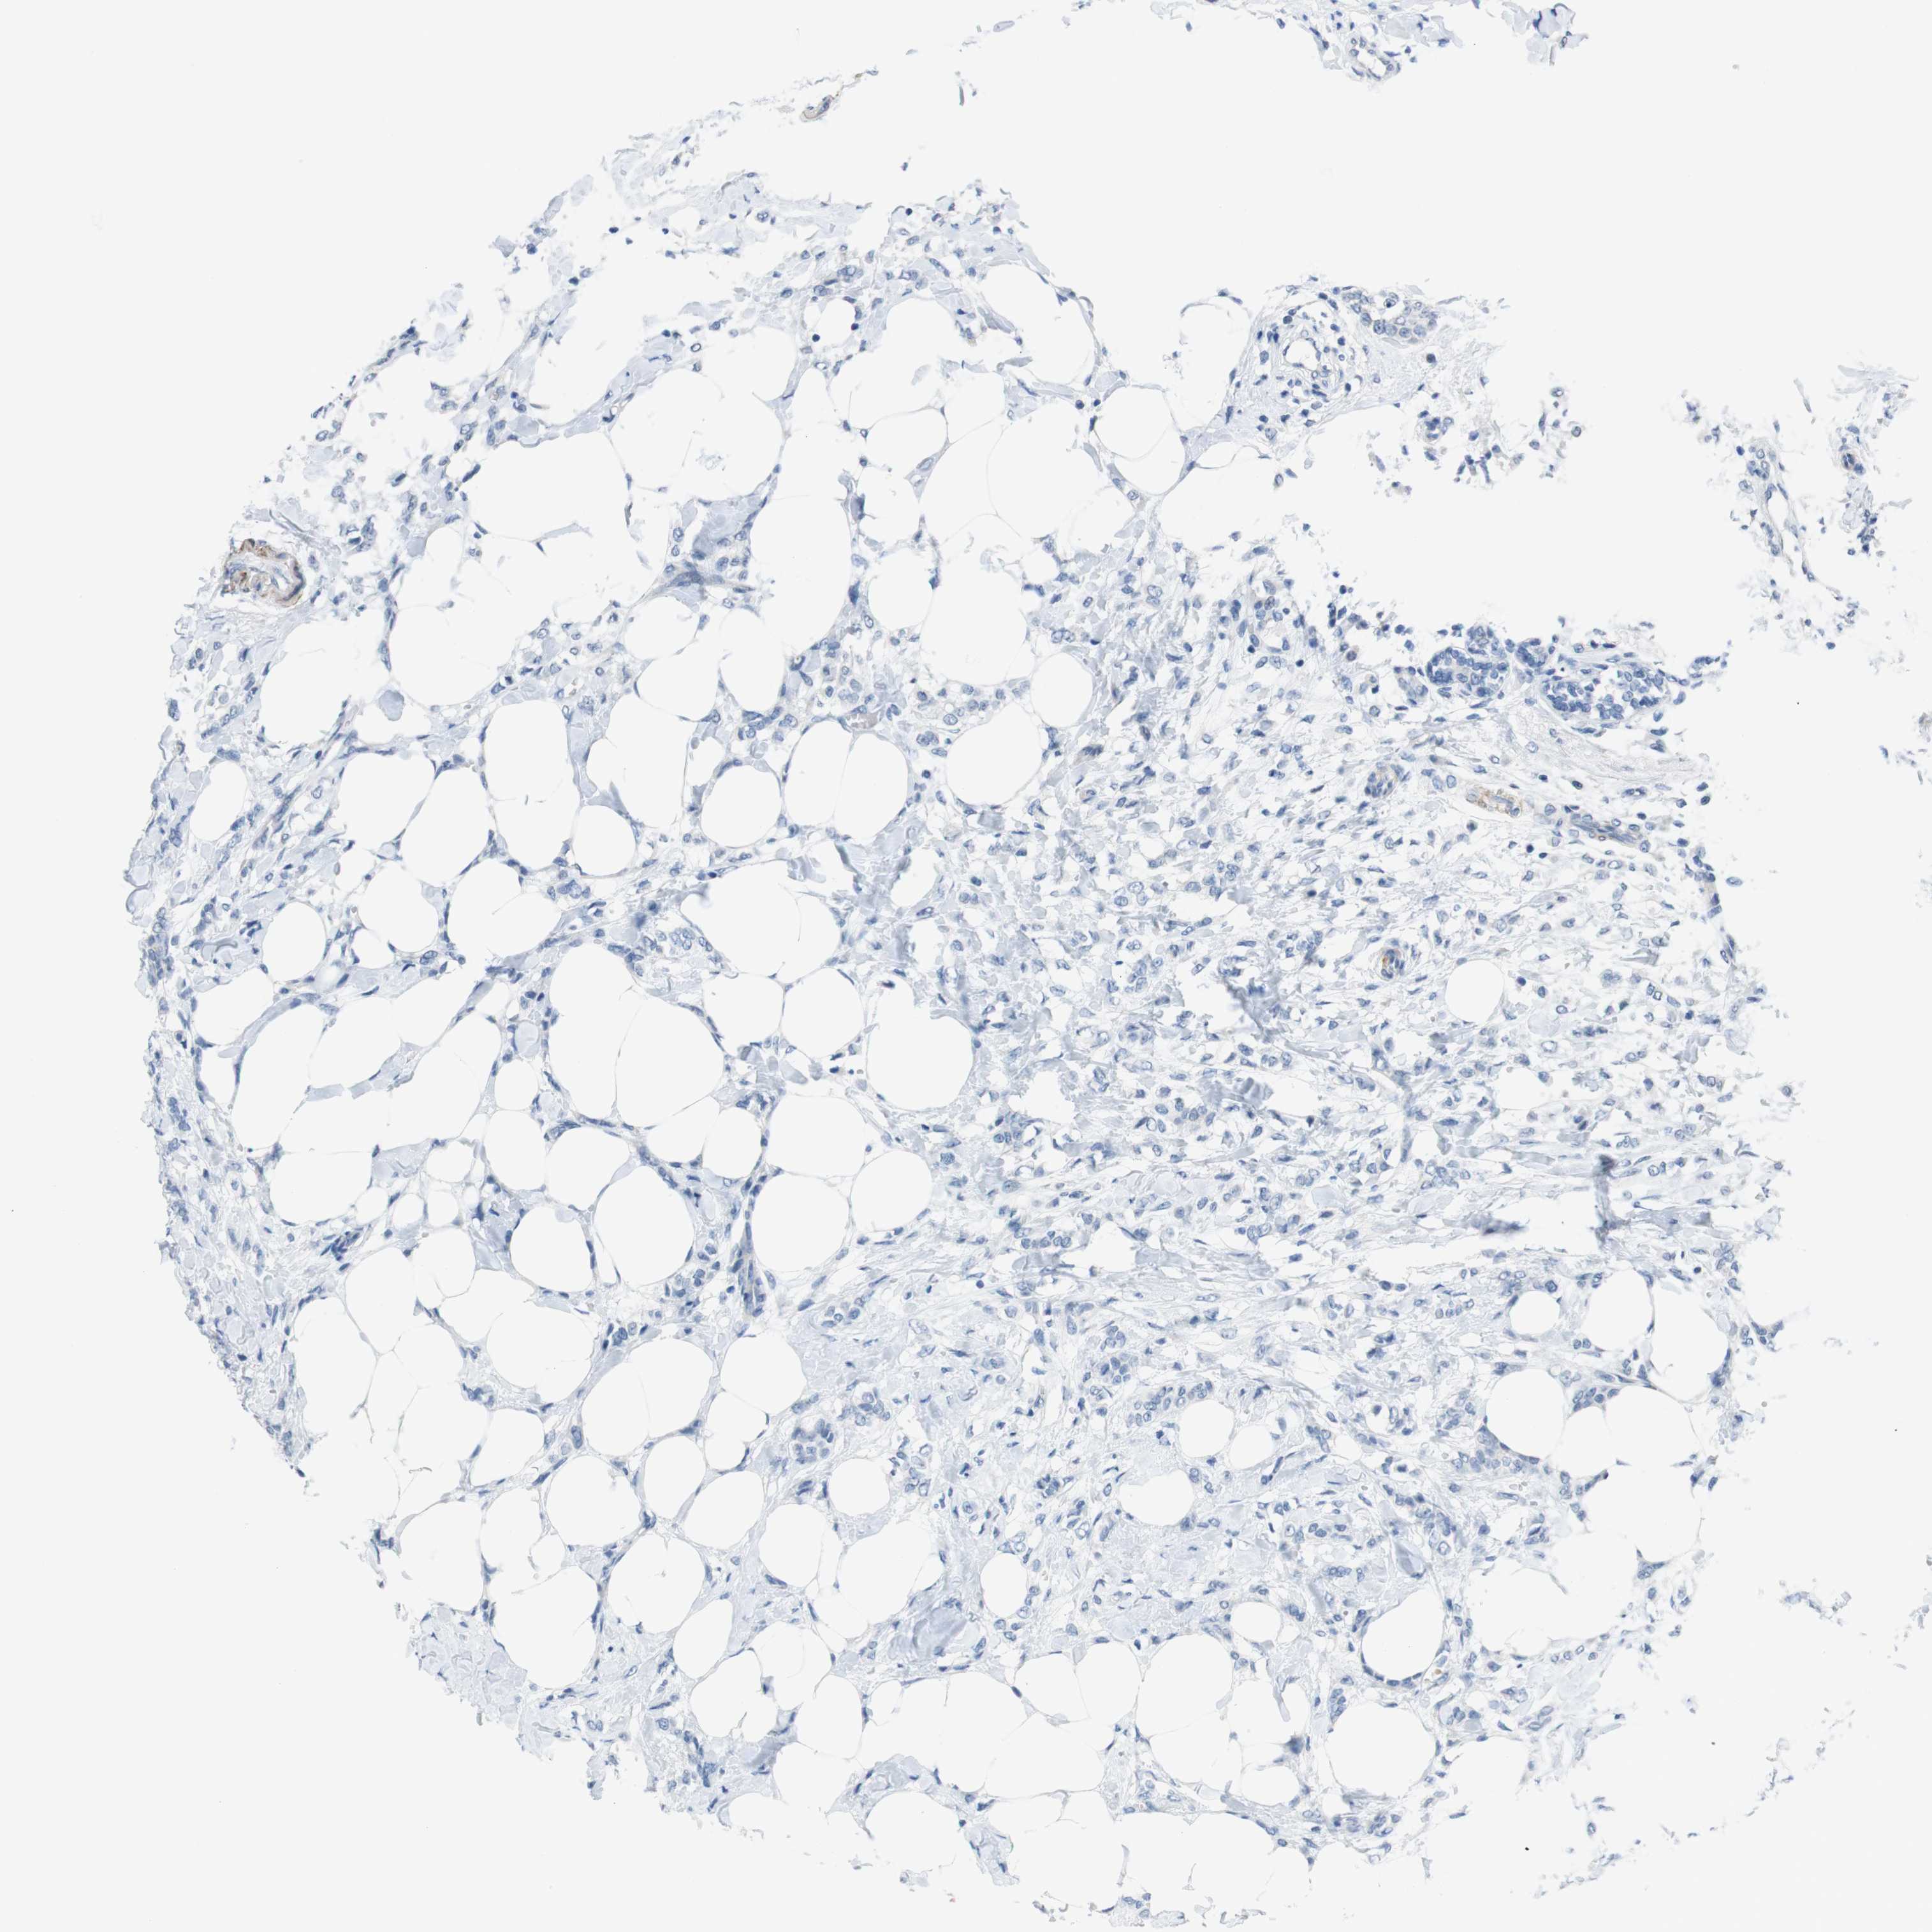

CANCER BREAST CANCER Show tissue menu

BRCA TCGA BRCA VALIDATION PROTEIN EXPRESSION

Breast cancer

Human cancer

Breast invasive carcinoma